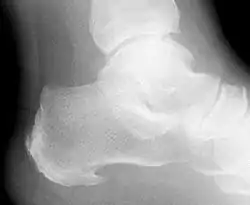

مسمار العظم أو مِهْمازُ العَقِب (أو ما يعرف عند كثير من الناس بمسمار الكعب[1]): هي نتوء عظميّ في عظم العقب تظهره الأشعة السينية يتكوّن عادة من التهاب اللفافة الأخمصية (أو ما تسمى بالرباط الأخمصيّ plantar fasciitis) والذي يسبب آلاماً في باطن القدم والكعب. ويتكون مهماز العقب من ترسب الكالسيوم.

![]() صورة بالأشعة السينية تبين شوكة عظمية صورة بالأشعة السينية تبين شوكة عظمية | |